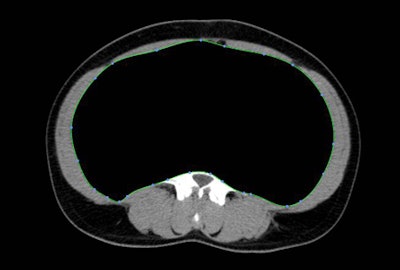

| When gender was ignored (chart above), patients on 6-MP had significantly less SAT overall, while patients on IFX had less VAT/SAT. Results segregated by gender (chart below) showed significant differences between genders for upper gastrointestinal disease, perianal disease, and IFX use. Significant differences were all found in female patients, and the chart also shows that patients with markers of severe disease have less VAT. |

![]() |